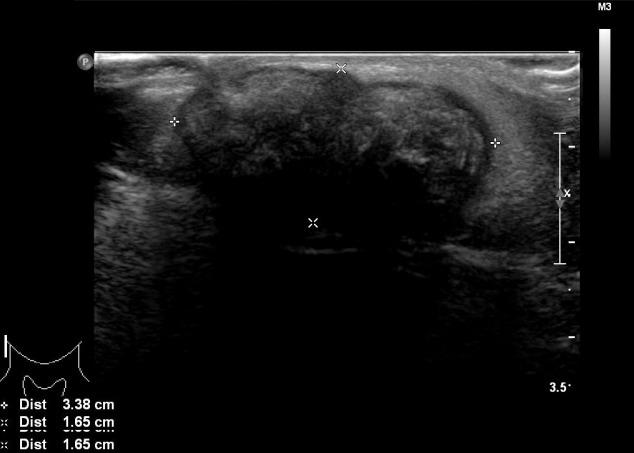

進(jìn)行超聲檢查以確定腫塊是否為腮腺腫瘤,并顯示與腮腺分離的異質(zhì)腫塊(圖 2)。 進(jìn)行了頸部對比增強(qiáng)計(jì)算機(jī)斷層掃描和超聲引導(dǎo)穿刺活檢。 在右下頜角,它表現(xiàn)為邊界清楚、分葉狀和不均勻強(qiáng)化的腫瘤,在皮下脂肪層和淺表肌肉腱膜系統(tǒng)中有鈣化部分(圖 3)。 穿孔活檢顯示與毛母質(zhì)瘤一致的特征,并且在超聲引導(dǎo)下對頸部淋巴結(jié)進(jìn)行抽吸活檢時(shí)未發(fā)現(xiàn)腫瘤細(xì)胞。

圖 2:超聲檢查顯示與腮腺分離的異質(zhì)性病變